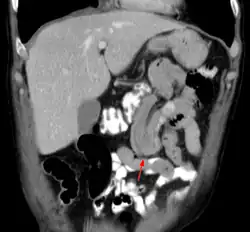

Durch eine Ultraschalluntersuchung lässt sich die Störung recht sicher feststellen, da die eingestülpten Darmteile eine zwiebelschalenartig aufgebaute Struktur (Zielscheiben- oder Target-Phänomen) bilden. Vor Einführung der Ultraschalluntersuchung wurde ein Einlauf mit Röntgenkontrastmittel unter Durchleuchtung zur Bestätigung der Diagnose und gleichzeitigen Therapie gemacht. Bei Erwachsenen kann auch die Computertomografie zur Diagnose führen.

Die diagnostische Standardmethode ist eine Computertomographie des Bauches[8] und die Sonografie.[7] Nicht selten wird die Diagnose auch erst gestellt, wenn zur Diagnosefindung der Bauchraum chirurgisch geöffnet wird (eine so genannte Probelaparatomie).